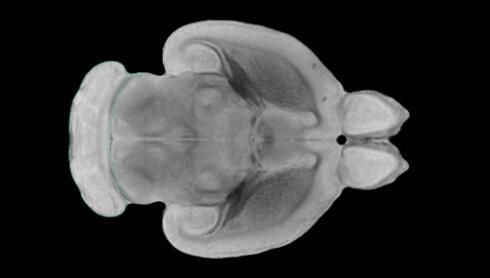

隨著機體年齡增加,肌肉和關(guān)節(jié)都會變得僵硬,這就會使得日?;顒幼兊酶永щy,本文研究表明,我們的大腦也是如此,與年齡相關(guān)的大腦僵硬對大腦干細(xì)胞的功能或許有著重要影響。文章中,研究人員對年輕和老化大鼠的大腦進(jìn)行研究闡明了年齡相關(guān)大腦僵硬對少突膠質(zhì)前體細(xì)胞(OPCs,oligodendrocyte progenitor cells)功能的影響。OPCs是一類對維持正常大腦功能非常重要的大腦干細(xì)胞,其對于髓磷脂的再生也非常重要,髓磷脂是神經(jīng)組織周圍的脂肪鞘,在多發(fā)性硬化癥中髓磷脂的再生常常會被損傷,機體老化對這些細(xì)胞的影響常常會誘發(fā)多發(fā)性硬化癥的發(fā)生,這些細(xì)胞的功能在老化的健康人群中同樣會下降。

為了確定老化OPCs的功能缺失是否可以被逆轉(zhuǎn),研究人員將來自老化大鼠機體的老化OPCs轉(zhuǎn)移到了年輕大鼠柔軟的海綿狀大腦組織中去,值得注意的是,這些老化的大腦細(xì)胞能夠重新恢復(fù)活力,其行為非常像年輕更加強壯的細(xì)胞。這項研究中,研究人員在實驗室中開發(fā)出了具有可變僵硬程度的新型材料,并在受控環(huán)境下研究這些材料的生長及其對大鼠大腦干細(xì)胞的影響,這些材料能被工程化改造具有和年齡或老化大腦相似的柔軟程度。